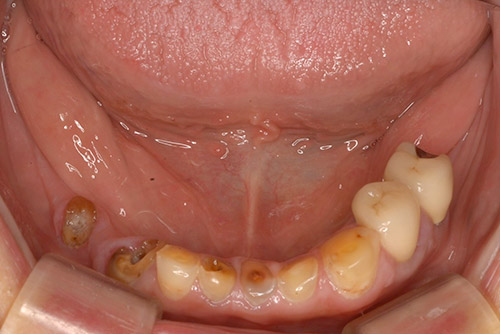

セラミッククラウン ノンクラスプデンチャー(チタン):60代 女性

治療前

治療後

| 治療名 | セラミッククラウン ノンクラスプデンチャー(チタン) |

|---|---|

| 患者情報 | 60代 女性 |

| 執刀医 | 大塚院長 |

| 治療内容 |

咬耗してしまった歯をセラミッククラウンで修復治療。 欠損部位はノンクラスプデンチャーを装着。 |

| 治療期間 | 7回 |

| 費用(税込) | セラミッククラウン:121,000円×5本 ファイバーコア:27,500円×5本 ノンクラスプデンチャー(チタン):660,000円 合計:1,402,500円 |

| 治療に対するリスク | ノンクラスプデンチャーは樹脂製のため柔らかさがあり、経年的に入れ歯の維持する力が緩くなる場合があります。 |